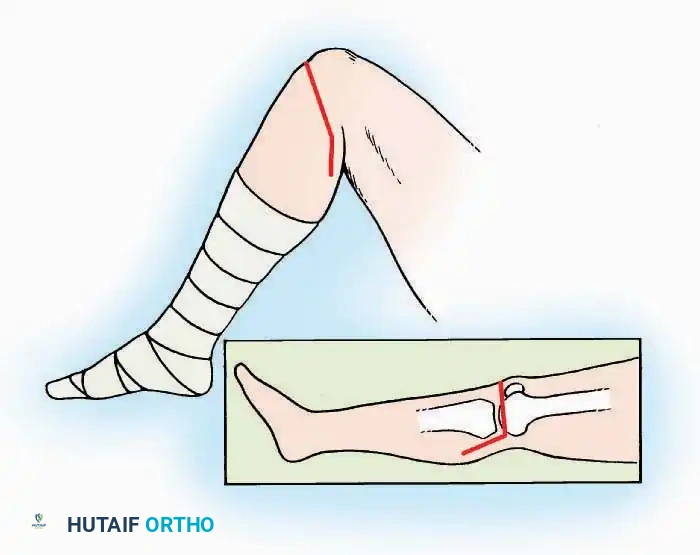

Postoperative Protocol Considerations